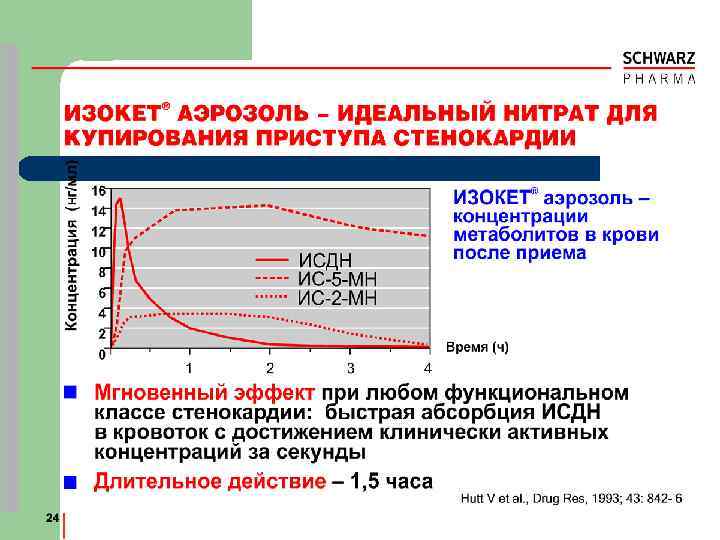

ИЗОКЕТ® l l -- Аэрозоль с насосом и дозатором (нет фреона) Прозрачный стеклянный флакон Индикатор маленького остатка Содержание флакона l 15 мл раствора l 375 мг ИСДН % l Пропиленгликоль l Этанол 89. 6 об. спрей

Тактика терапии нитратами l l I ФК – спрей-формы только по факту и/или перед предсказуемыми приступами II ФК – нитроглицерин за 5 мин или нитросорбид за 30 мин перед предполагаемой физической нагрузкой III ФК – изокет-ретард или мононитраты утром IV ФК – изокет-ретард или мононитраты утром и вечером